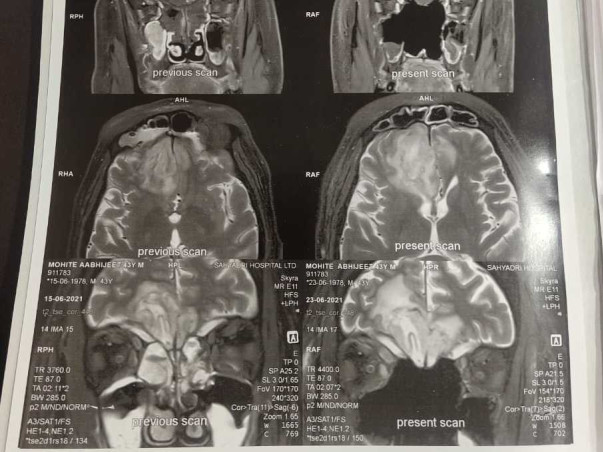

He is suffering from Mucormycosis (Black fungus) from the past few weeks. He is currently admitted and receiving ICU Care in Sahyadri Hospitals, Pune, Maharashtra.